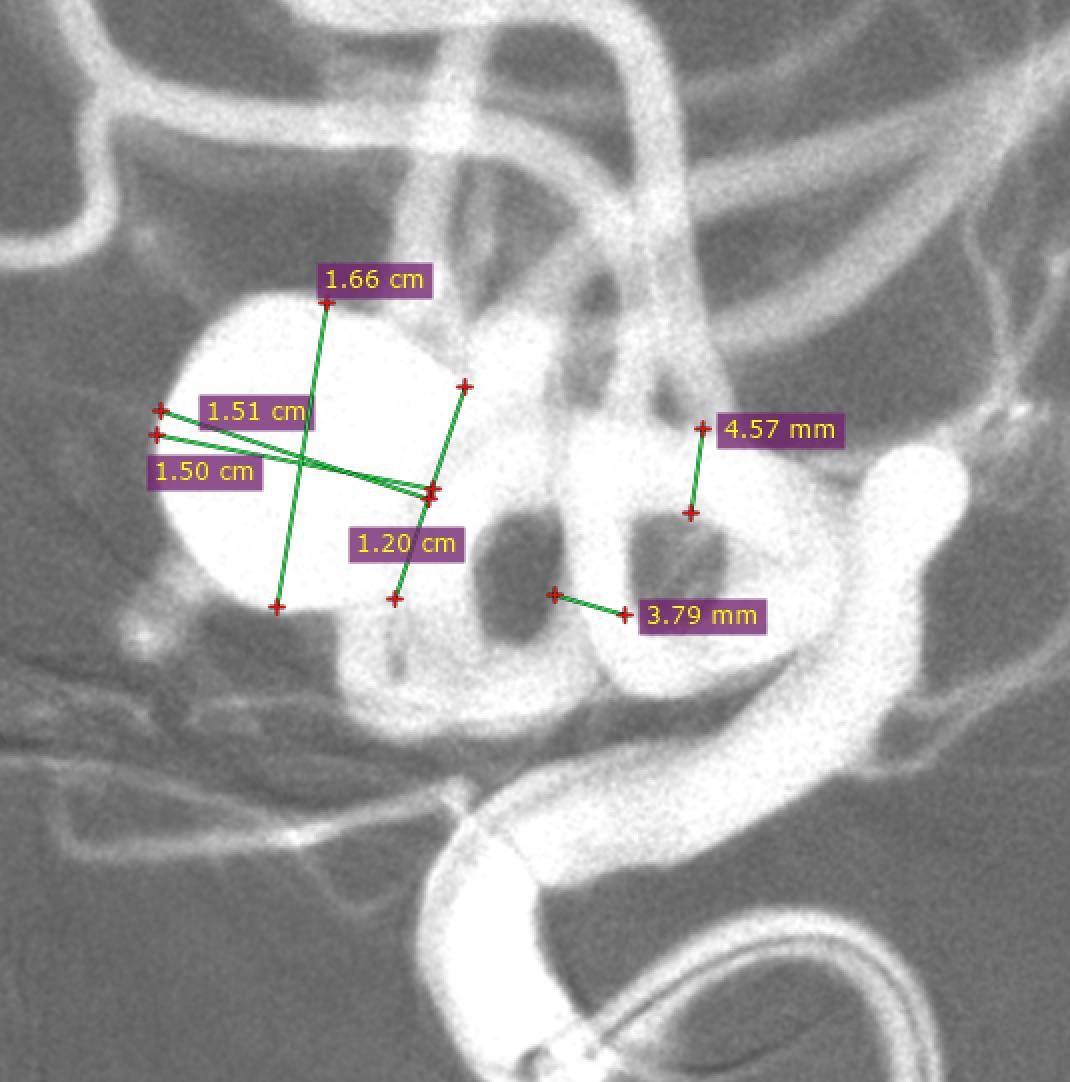

术前影像

术前正位DSA

术前侧位DSA

术前核磁

初步诊断:左侧大脑中动脉M1段动脉瘤

侧别、位置:左侧

动脉瘤的形态:囊性

动脉瘤大小:长24.8mm、宽23.1mm、高20mm

动脉瘤颈宽度:6.2mm

载瘤动脉直径:远端3.1mm,近端3.9mm